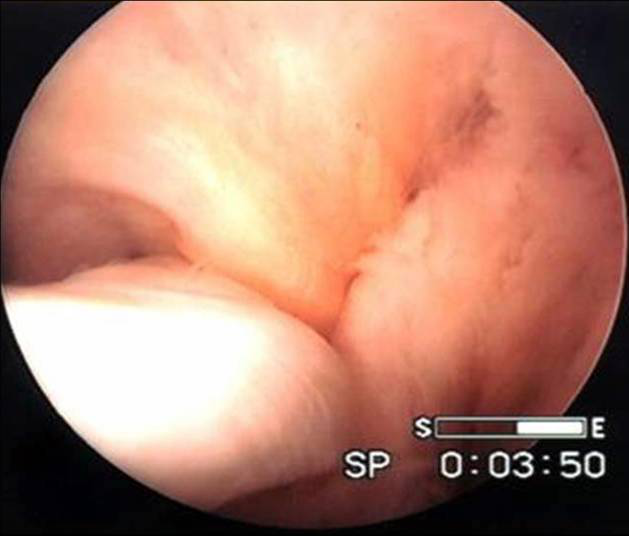

盤狀半月板完全型

不完全型盤狀半月板

盤狀半月板的切除-鏡下解剖

v盤狀是畫盤的盤,象蠶豆,不是園盤的盤。由于緊挨者ACL,前角處有梨把凹陷與ACL緊密相貼。外側(cè)有腘肌腱和滑膜緣關(guān)節(jié)囊,前后角都基本在中線前后1/3處。

v所以要以ACL、腘肌腱、外緣關(guān)節(jié)囊為解剖標志,隔開ACL、腘肌腱,而外緣留多少無所謂,注意ACL、腘肌腱的損傷。外緣用刨刀再處理。